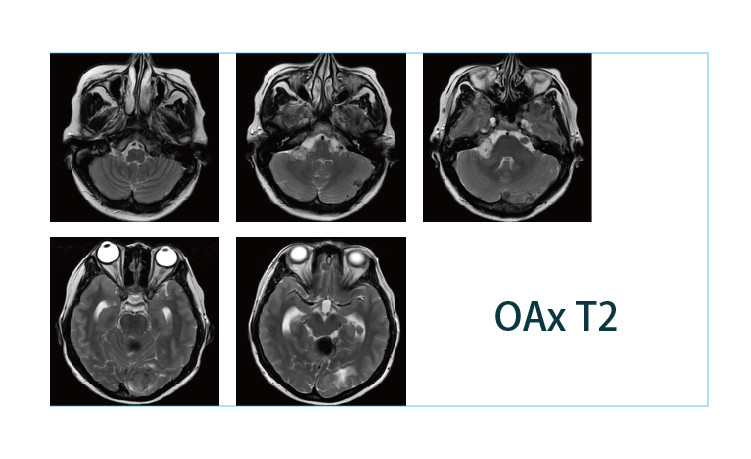

【朗润影像档案】20190419磁共振影像病例结果讨论

【朗润影像档案】磁共振影像病例分享(编号20190419)